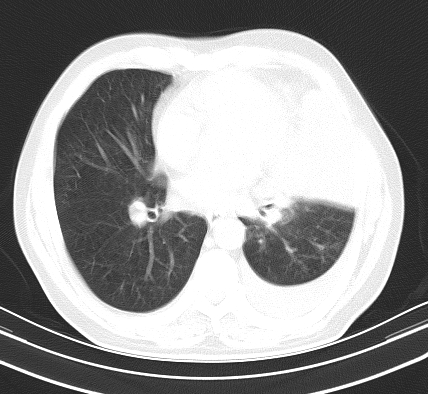

以下是引用老爱克斯新网客在2008-7-31 6:30:00的发言:[br]左肺上叶大片状病灶,左肺上叶支气管狭窄呈鼠尾状,左肺门增大,纵隔内见肿大淋巴结,左侧胸腔积液,余肺清晰。左肺中心型肺癌淋巴结转移,

以下是引用zjb在2008-7-31 6:32:00的发言:[br]左侧中心性肺癌 阻塞性肺炎 肺不张 胸腔积液 建议气管镜

以下是引用zjzjr在2008-7-31 8:45:00的发言:[br]考虑左侧中心性肺癌伴阻塞性肺炎,左肺上叶肺不张,纵隔淋巴结转移;左侧胸腔积液。建议行纤支镜检查。

以下是引用sdzyy在2008-7-31 8:47:00的发言:[br]病灶较治疗前有所进展,胸水增多, 左侧中心性肺癌 并 阻塞性肺炎 肺不张 胸腔积液 可能性大; 建议气管镜检查。 [br] [br]